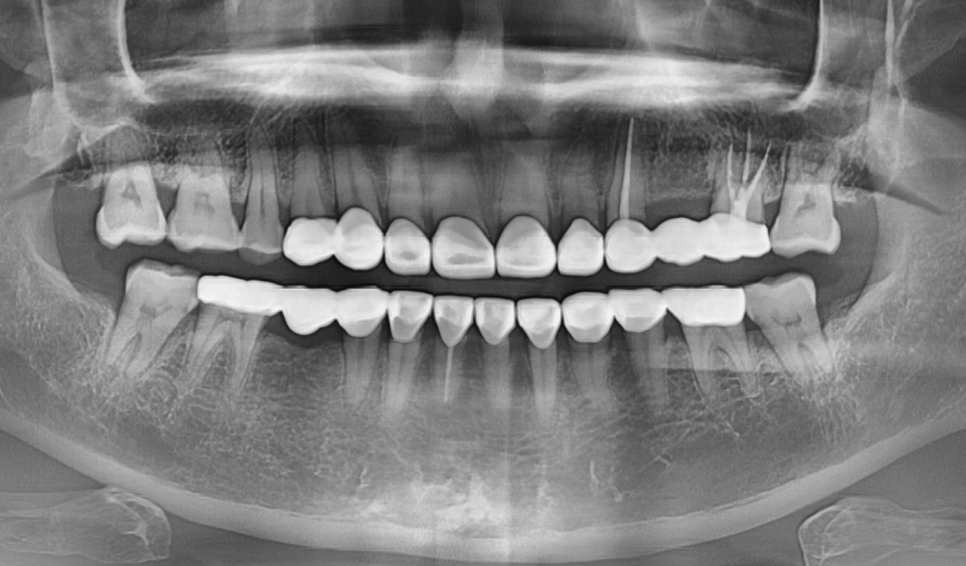

그렇게 최종 완성된 치아

누런 치아 연예인치아 처럼 하얗게 만들 수 있나요?

이런 극적인 변화는 치아미백으로는 절대 불가능합니다.

반면 크라운은 색이 변하지 않아 영구적으로 하얀색을 유지하기 때문에 만족도가 높습니다.

완성 후 환자분의 얼굴 전체 인상이 환해졌습니다.